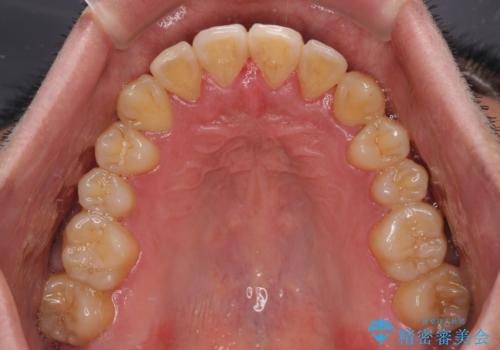

八重歯とクロスバイト 目立たないワイヤー装置で矯正治療

- 八重歯と前歯のクロスバイトを改善したいとのことで来院された患者様です。

デコボコの程度は強かったのですが、口元の突出感はなかったため、非抜歯矯正としました。

デコボコが解消されると歯列が拡大される方向に動くため、出っ歯のような仕上がりとなることがあります。舌の突出癖を改善するトレーニングをしっかりと行っていただくことで、突出を抑制することができます。